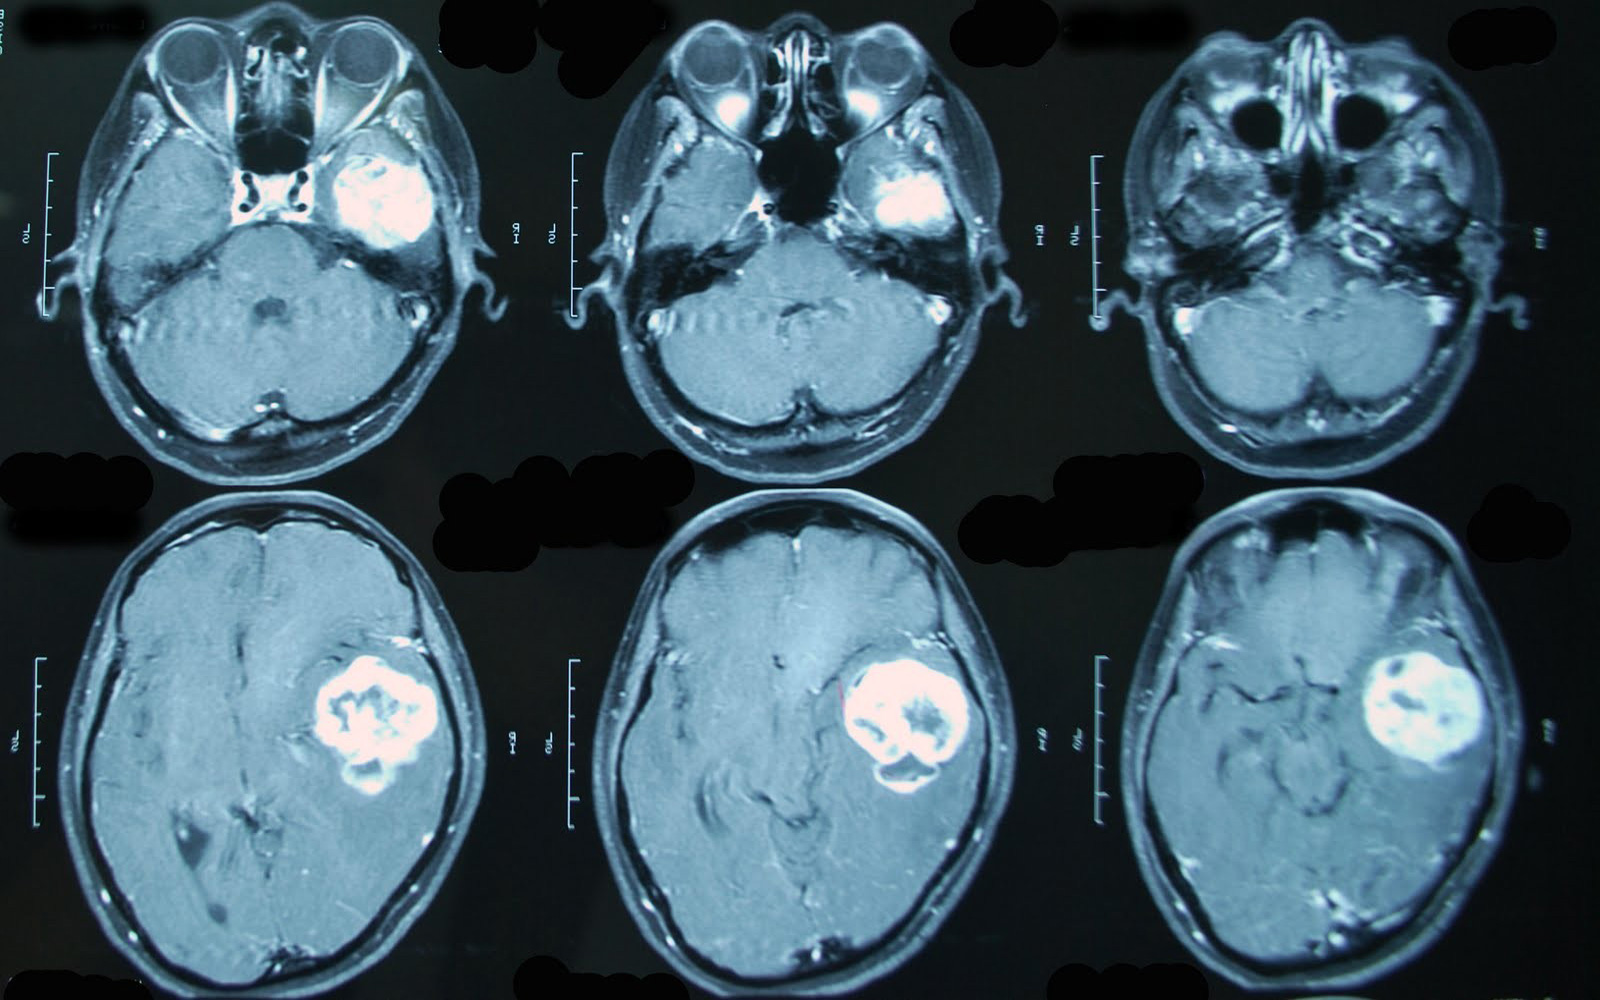

С помощью компьютерной томографии (КТ) исследуют практически все внутренние органы с получением их детального послойного изображения с толщиной среза от 0,5мм до 10мм. Компьютерная томография выполняется когда нужны максимально надежные визуализирующие методики. Полученное трехмерное изображение позволяет увидеть в подробностях топографию органов пациента, локализацию, протяженность и характер очагов заболеваний, их взаимосвязь с окружающими тканями.

1. головы, в том числе околоносовых пазух, орбит и височных костей, ангиография сосудов головного мозга;